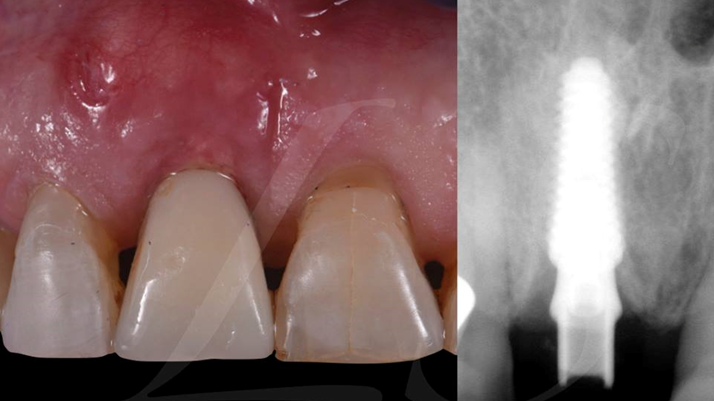

Clinical case: Extraction, immediate placement & loading using

R2GATE solution in aesthetic zone

- Courtesy of Dr. Jong-Cheol Kim, Korea-